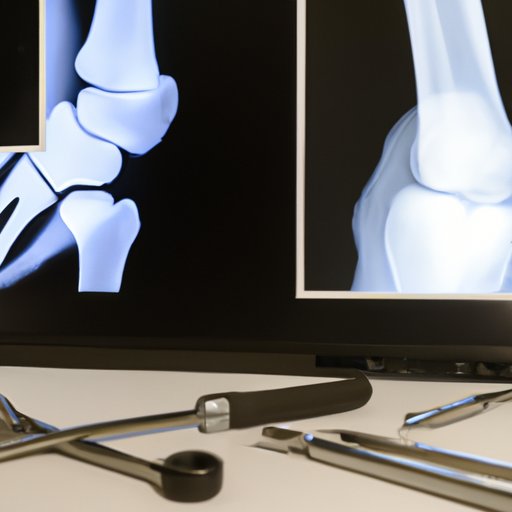

Can arthritis be seen on an X-ray? This article...